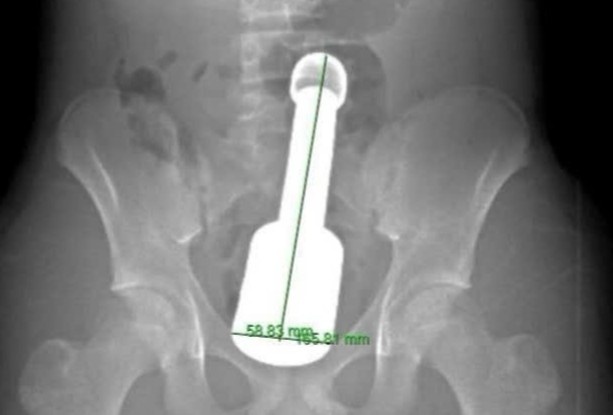

Hình ảnh phim chụp X-quang cho bệnh nhân.

Bệnh nhân N.K.N. (15 tuổi, Hà Đông, Hà Nội) được đưa tới Bệnh viện Đa khoa Hà Đông trong tình trạng đau tức dữ dội vùng hạ vị. Kết quả chụp X-quang cho thấy một dị vật kim loại kích thước lớn nằm sâu trong trực tràng, chèn ép các cơ quan vùng chậu.

Sau khi đánh giá kỹ lưỡng, các bác sĩ quyết định lấy dị vật qua đường hậu môn nhằm tránh phải mổ mở ổ bụng. Tuy nhiên, thử thách không hề nhỏ. Dị vật là một chiếc chày dài khoảng 18 cm, đường kính 6 cm - gần chạm ngưỡng tối đa mà cơ thắt hậu môn của một thiếu niên có thể giãn ra.